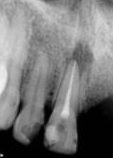

antes depois